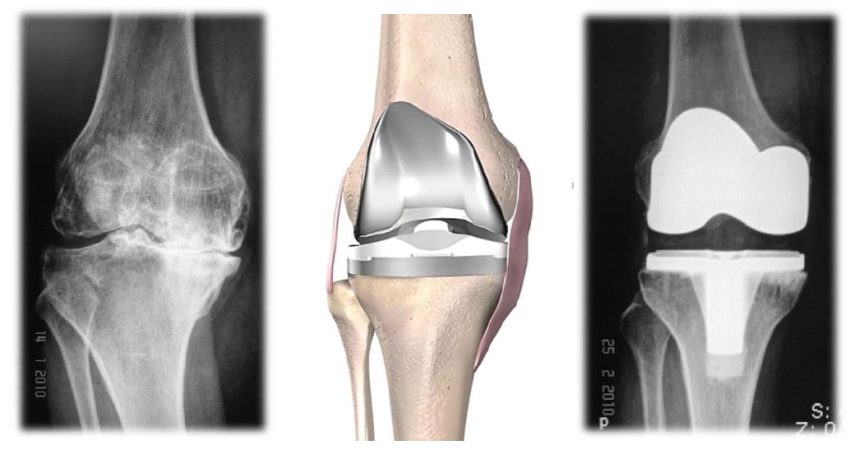

คือโรคที่เกิดจากการสึกกร่อนของกระดูกอ่อนผิวข้อ ซึ่งเป็นผลมาจากอายุที่เพิ่มขึ้นและ การใช้งานมาก ผิวข้อที่สึกจะมีการขัดสีกัน ทําให้ให้เกิดอาการปวดเข่าตามมา

การผ่าตัดเปลี่ยนข้อเข่าเทียมในผู้ป่วยโรคข้อเข่าเสื่อม

การผ่าตัดเปลี่ยนข้อเข่าเทียมคืออะไร คือการผ่าตัดเพื่อนผิวข้อเข่าเดิมที่เสื่อมสภาพออก และทดแทนผิวข้อใหม่ด้วยข้อเข่า เทียม ควรพิจารณาผ่าตัดเปลี่ยนข้อเข่าเทียมเมื่อใด ผู้ป่วยโรคข้อเข่าเสื่อมที่รับการรักษาด้วยวิธีการไม่ผ่าตัด

ประสบการณ์หลังการผ่าตัดเปลี่ยนข้อเข่าเทียม

ข้อเข่าและข้อสะโพกเทียม